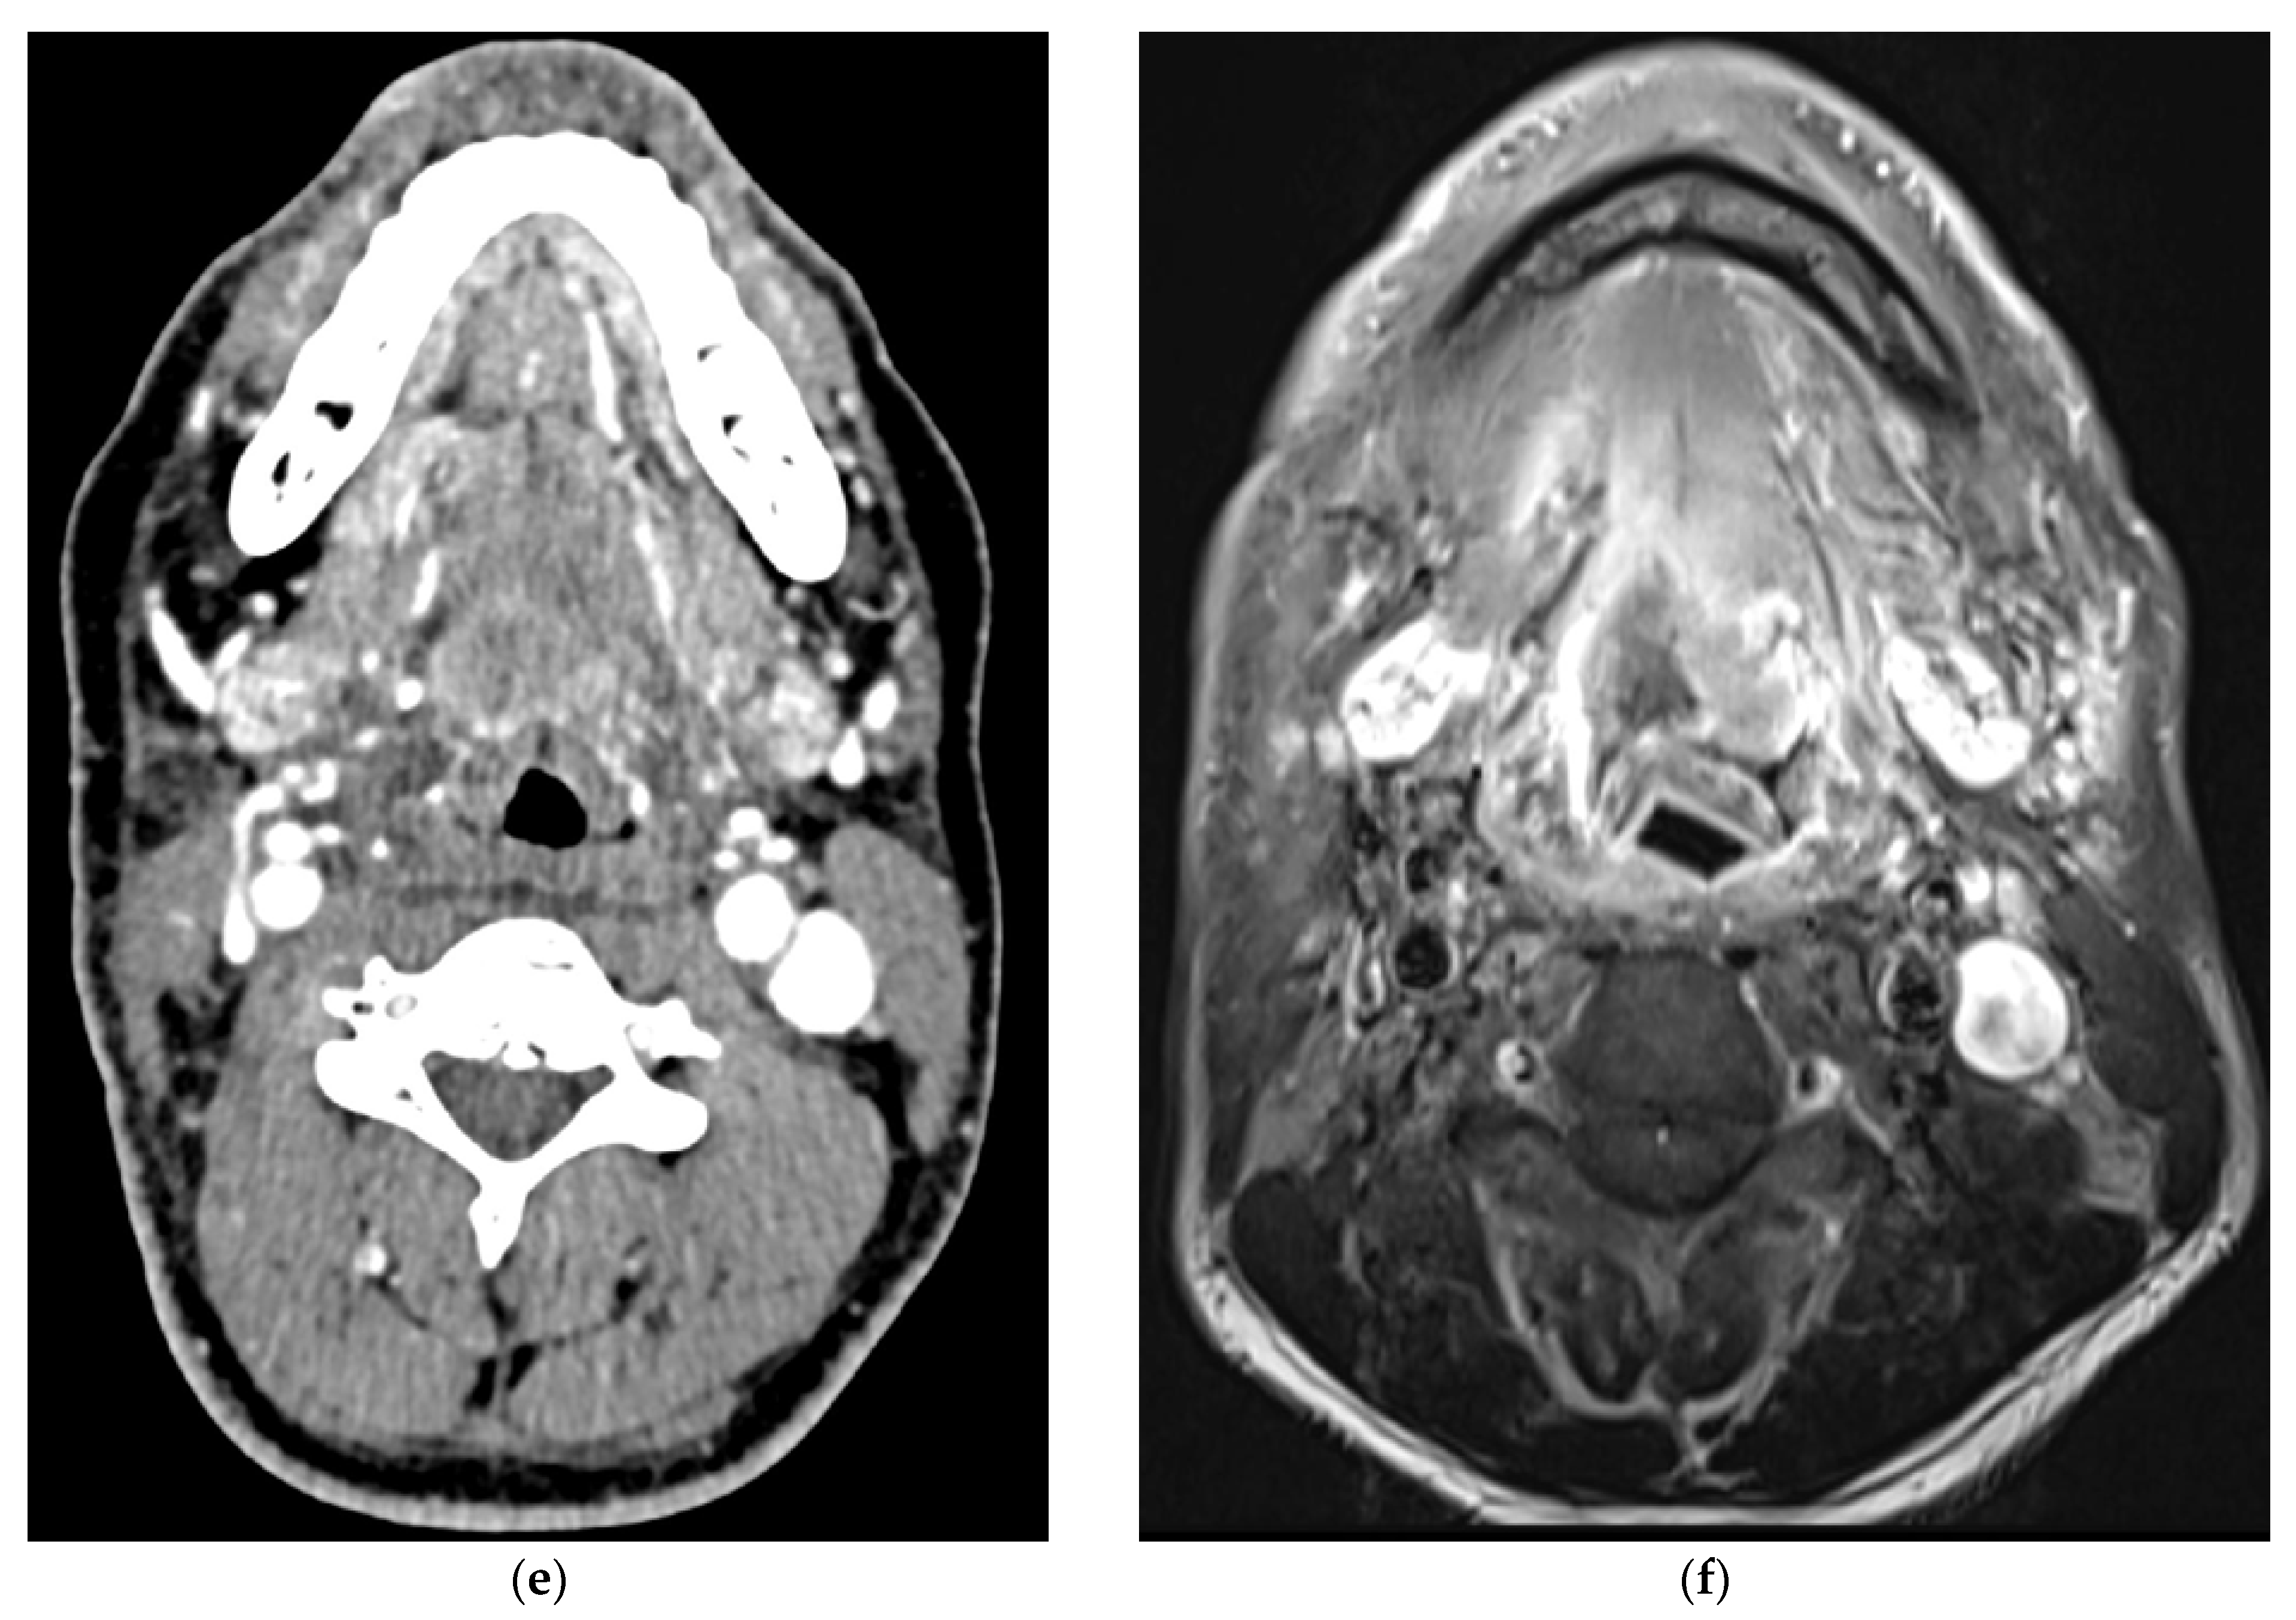

5. Imaging of Oropharyngeal Cancers

8.1. Initial Staging